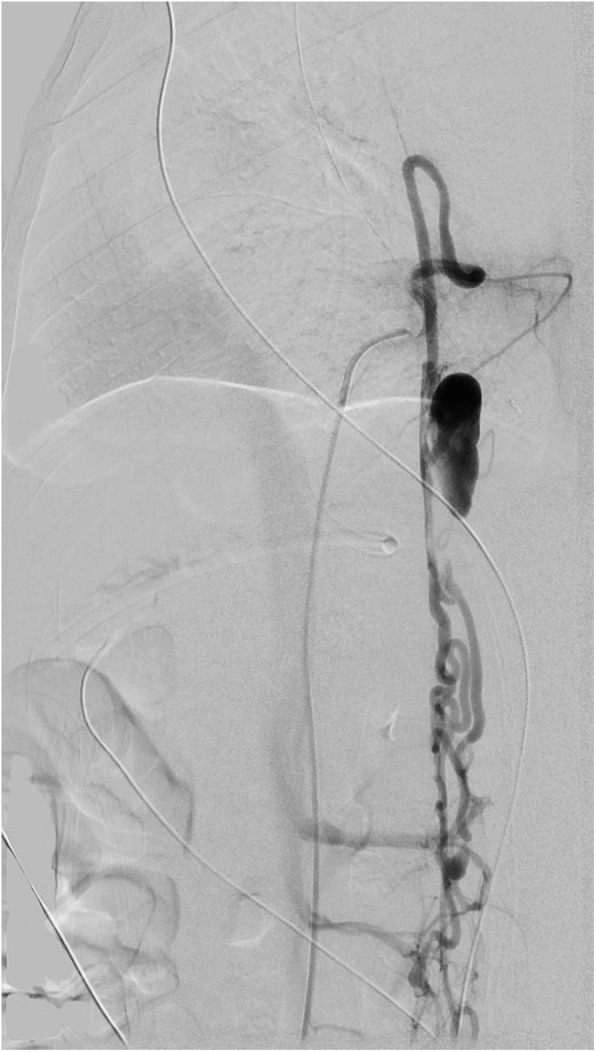

The emergent angiogram was performed under general anesthesia. Patient received combined intravenous and inhalation induction with propofol and sevoflurane. Two large bore IVs were established in anticipation of blood loss. The patient was found to have a complex type IVc AVM (Fig. 2) and fistula from the Artery of Adamkiewicz at L1-L2. She also had perimedullary dilated veins and a pseudoaneurysm that measured 2.5 cm × 1.5 cm × 1.5 cm. The pseudoaneurysm compressed the spinal cord at T8-T10 (Fig. 3), displacing it from right to left.

Fig. 2.

Digital subtraction angiogram in lateral projection of the injection of the anterior spinal artery at T8 with its hairpin turn feeding the AVM and the pseudoaneurysm which extends from T9 to T12. The venous plexus is contrast filled inferiorly with opacification of the draining veins and slight opacification of the IVC